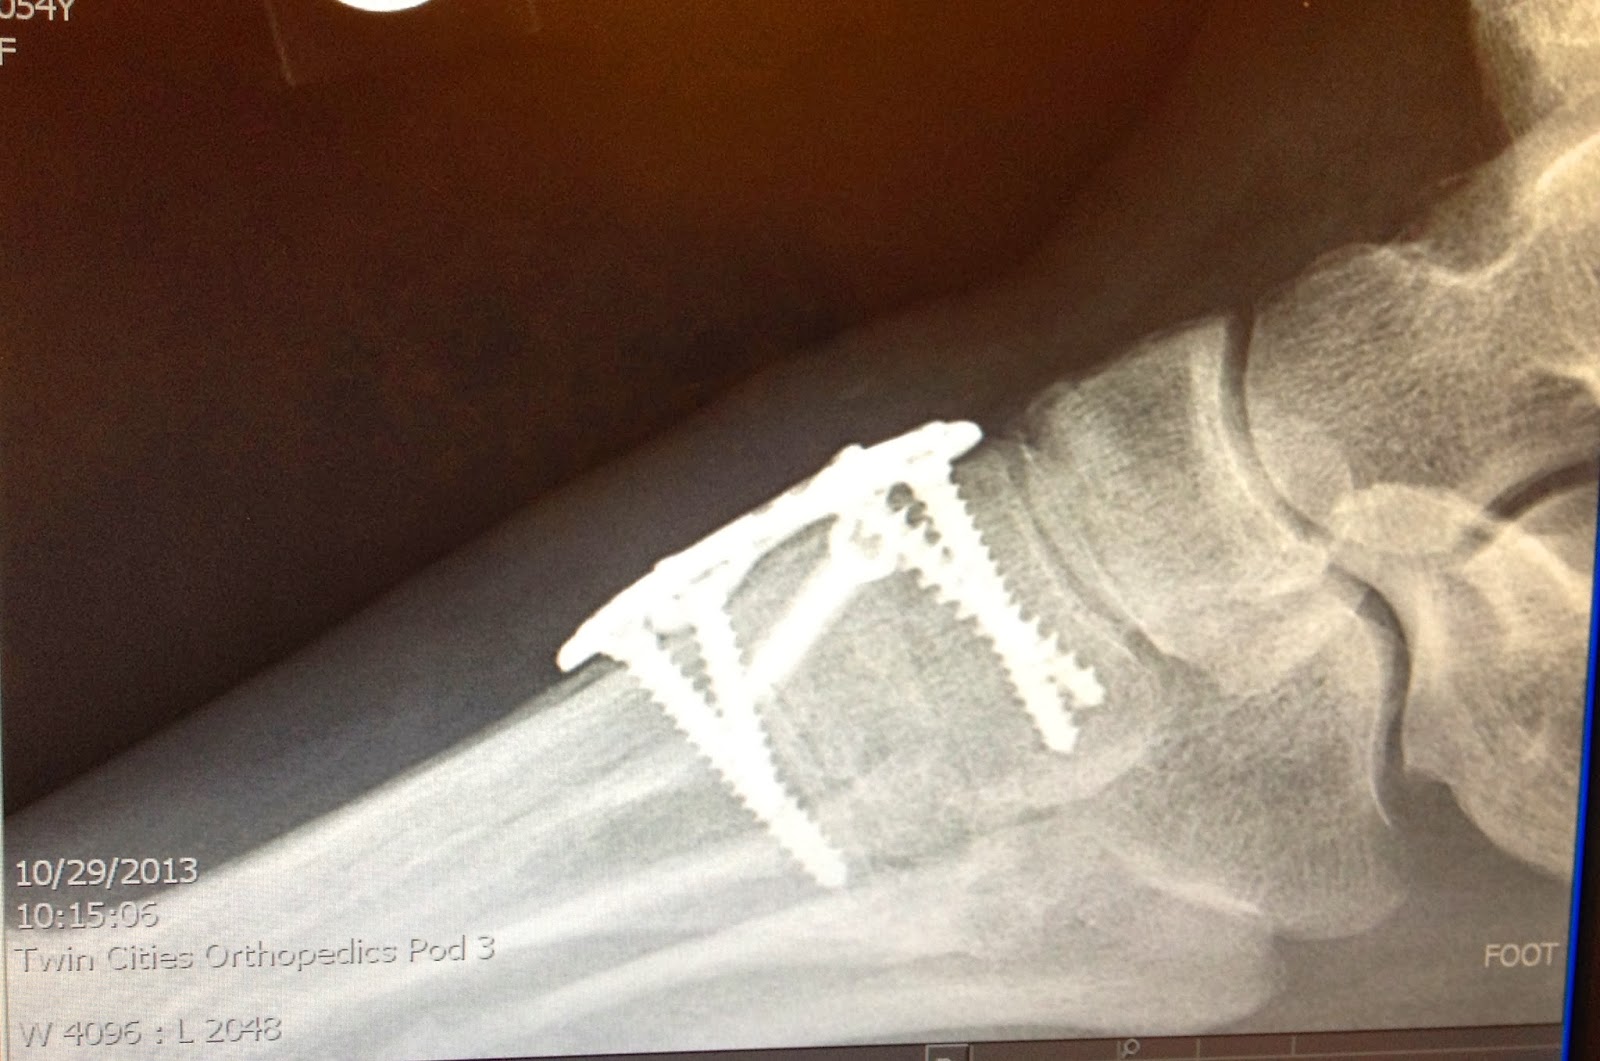

After LisFranc Surgery Weekly Lisfranc Surgery images during recovery Can You Play Sports After Lisfranc Surgery Lisfranc injuries can occur in a wide array of scenarios including motor vehicle accidents (43%), falls from heights (24%), crush injuries. Lisfranc injuries can be particularly devastating to competitive athletes. Athletes can injure their lisfranc joint playing sports, but even a small stumble or tripping throughout your day can cause an injury. They can dramatically hinder athletic performance, cause severe.. Can You Play Sports After Lisfranc Surgery.

From lisfrancsurgery.blogspot.com

After LisFranc Surgery New technology for Lisfranc injuries and fusions Can You Play Sports After Lisfranc Surgery We hypothesized that open reduction and screw fixation of a ligamentous. Athletes can injure their lisfranc joint playing sports, but even a small stumble or tripping throughout your day can cause an injury. Lisfranc injuries can be particularly devastating to competitive athletes. Research findings indicate that most athletes can successfully return to normal play after lisfranc sports injuries, with a. Can You Play Sports After Lisfranc Surgery.